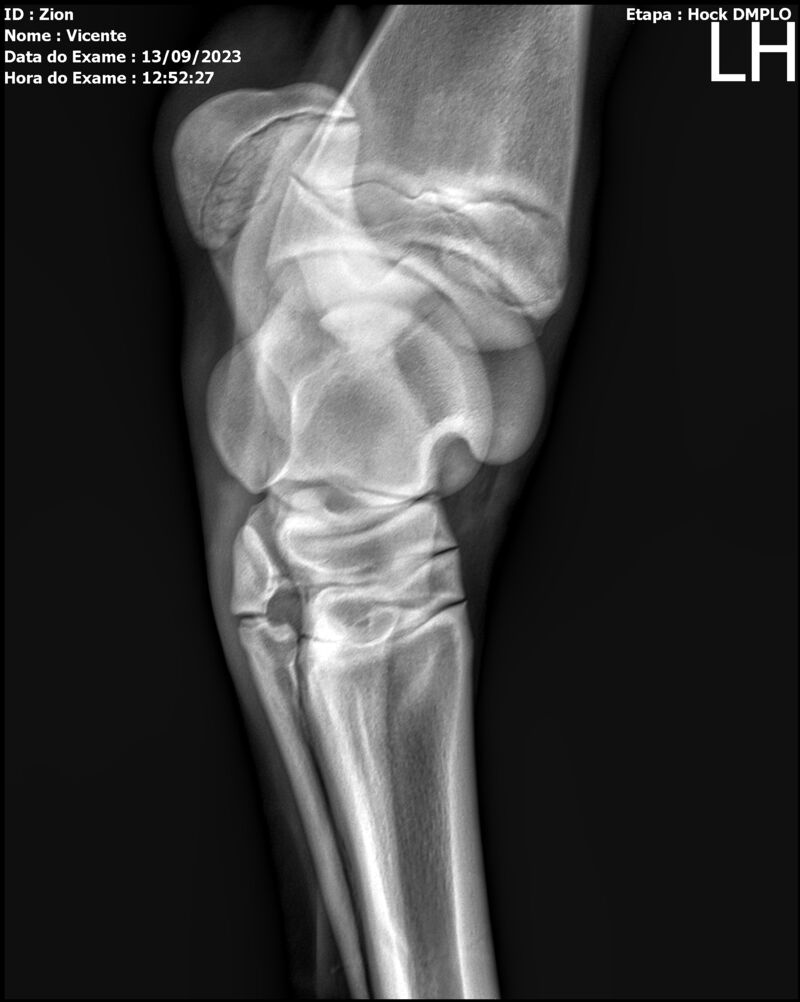

ZION ZC

Raça: BRASILEIRO DE HIPISMO

Sexo: MACHO - POTRO

Nascimento: 17/12/2022

Altura Aproximada: 1,51

Pel.: CASTANHO

Registro: EM AND

Vend.: VICENTE CONTE

Local : PORTO FELIZ/SP